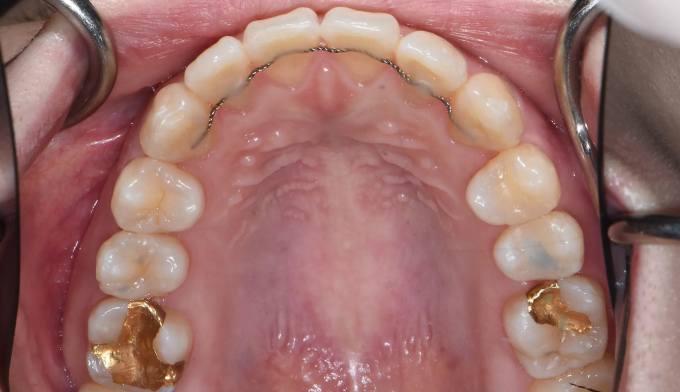

After

윗니는 아랫니를 약 2mm 내외로 덮는것이 심미적으로, 그리고 기능적으로 제일 이상적입니다. 하지만 여러 요인으로 인해 윗니가 아랫니를 절반이상 덮는 경우를 과개교합이라고 부릅니다.

과개교합은 윗니에 무리한 힘이 가해지게 될 수 있고, 앞니의 마모 속도 또한 빨라질 수 있으며 이는 턱관절 문제까지 이어질 수 있습니다.

총 교정기간은 19개월입니다.